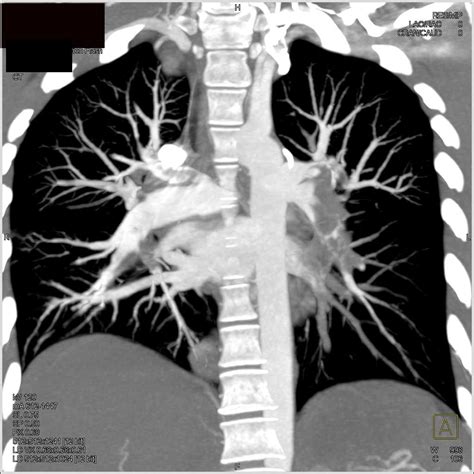

Computed Tomography (CT) Scan

A CT scan provides more detailed images of the lungs and can detect the presence of a blood clot in the pulmonary arteries. This test is often used to confirm a diagnosis of lung embolism. During a CT scan, a contrast dye is injected into a vein, which helps to highlight the blood vessels and make any blockages more visible.